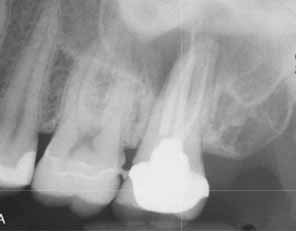

上顎小臼歯と大臼歯の歯根は副鼻腔底に近くにあり、根尖性歯周炎では骨の境界が緩み、細菌が上顎腔に侵入して副鼻腔炎を引き起こす可能性があります。抜歯、顎外科手術、インプラント埋入では、口腔と上顎洞の間に急性的な交通路が残ることがあります。その結果、いわゆる口腔前庭部に口腔上顎洞瘻を形成し、そこから膿が排出され、それが副鼻腔への微生物の侵入点となり、細菌の定着や感染につながる可能性があります(画像2a、2b)。

- 小臼歯/大臼歯領域の歯根尖/歯周領域における放射線透過性(画像3a、画像3b)

- 歯根尖/歯周領域における放射線透過性を示すCTスキャン(画像3c)